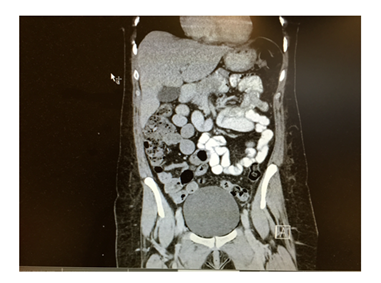

Her inflammatory markers were raised with C reactive protein (CRP) reading at 150 mg/L and White cell count of 10.2X 109. Erect chest X-ray showed large amount of air under the diaphragm and abdominal X-ray showed dilated small bowel loops (Figure 2) in the left upper quadrant and free air between the loops. The patient underwent emergency laparotomy with hissing of air escape at peritoneal opening. All organs were examined and no abnormality was seen. All four quadrants examined thoroughly but no evidence of any bowel leak found. There were no signs of any inflammation in pelvis and a negative laparotomy was concluded. The patient had uneventful recovery and was discharged home on 4th post-operative day. The patient underwent further abdominal and pelvic CT scan Figure 3-5 with contrast few days after the operation for completion of investigation and no abnormality was seen. The patient was reviewed in the clinic one and three months after the operation with no complaint and no post-operative complications.

Figure 3 Dilated bowel loops and free air.

Figure 4&5 Normal follow up CT scan.